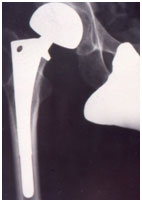

B. 頚部内側骨折

骨頭への血流が得られにくいため、原則として人工骨頭挿入術 を行います。これにより、早期に荷重をかけることが可能となり、手術翌日からリハビリを開始します。手術2日目には車いすでの移動や歩行訓練も行い、早期の日常生活復帰を目指します。

合併症としては、人工骨頭の脱臼のリスクがあります。そのため、股関節の深屈曲をしないよう、リハビリや日常生活の指導を行っています。